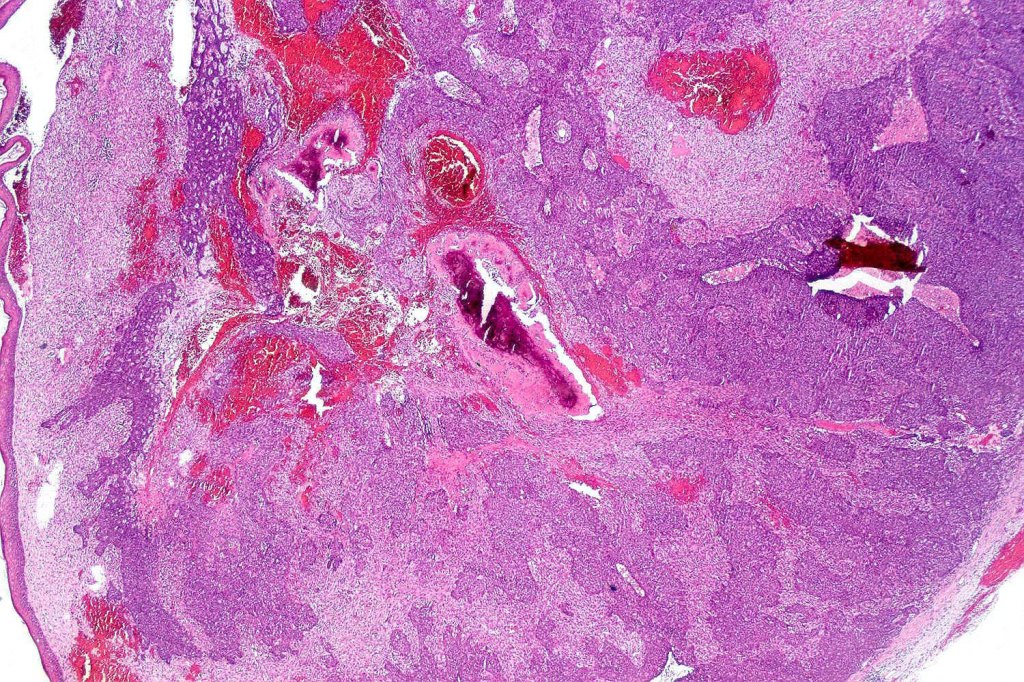

Carcinosarcoma

Cutaneous carcinosarcoma (metaplastic carcinoma, carcinoma with heterologous differentiation)

Histological features

•Osteoid

•Chondroid

•Smooth muscle

•MFH-like features with osteoclasts

•Neural differentiation